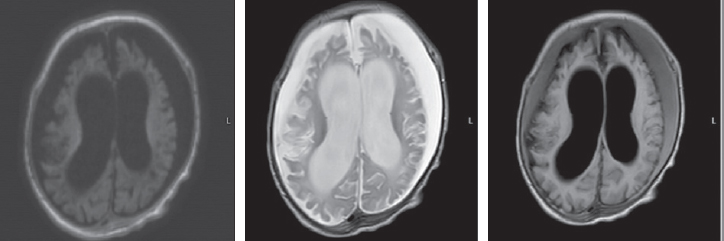

The child’s condition remained critical, with impaired consciousness, extension contractures in the elbow and knee joints, and non-epileptic paroxysmal states, such as bronchospasm and apnea persisting. Startle reflexes were pronounced and with any tactile stimulation, startle (generalized myoclonus) was registered. With the progression of neurological disorders, an increase in the cystic-atrophic changes was noted and hydrocephalus was formed. The data of MRI over a time, performed at the age of four months, are presented in Fig. 3.

Fig. 3. Magnetic resonance imaging of a patient at the age of 4 months. Axial sections, T1 VI, T2 VI, Flair. There is a negative dynamics in the form of cystic-atrophic changes in the large hemispheres of the brain with the formation of atrophic hydrocephalus. The appearance of symmetrical subshell clusters in the form of subdural hygromas

Рис. 3. Магнитно-резонансная томограмма пациента в возрасте 4 мес. Аксиальные срезы, Т1ВИ, Т2 ВИ, Flair. Наблюдается отрицательная динамика в виде кистозно-атрофических изменений в больших полушариях головного мозга с формированием атрофической гидроцефалии. Появление симметричных подоболочечных скоплений в виде субдуральных гигром